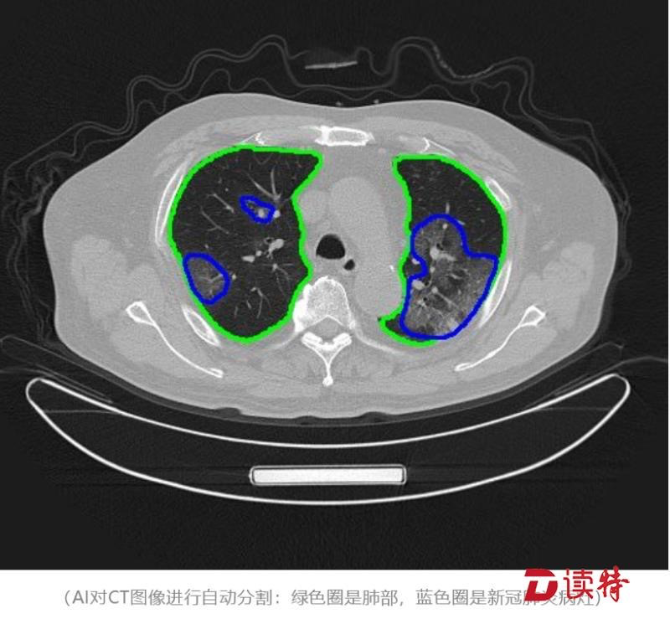

“騰訊覓影”AI輔助診斷

疫情伊始,云天勵(lì)飛研發(fā)的人工智能紅外測(cè)溫設(shè)備及系統(tǒng),可以快速識(shí)別發(fā)熱患者,有效提高檢測(cè)效率,在國(guó)務(wù)院聯(lián)防聯(lián)控機(jī)制新聞發(fā)布會(huì)上被點(diǎn)名表?yè)P(yáng);騰訊用“騰訊覓影”AI輔助醫(yī)生提高CT檢查效率;普渡科技提供 “歡樂送”智能配送機(jī)器人,負(fù)責(zé)服務(wù)臺(tái)問詢、導(dǎo)診、送餐等任務(wù),甚至醫(yī)院里高風(fēng)險(xiǎn)的消殺工作;大疆無人機(jī)協(xié)助交警開展執(zhí)勤管控。